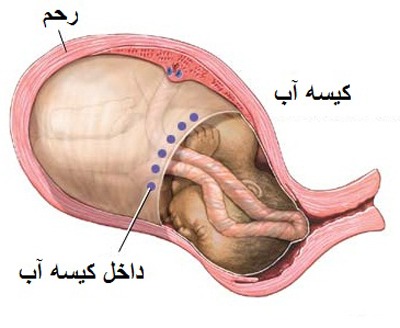

بیشتر بخوانید »کمبود آب دور جنین + راههای درمان

باردار بودن حس خوبی دارد درست است؟ شما سرشار از شادی و لذت هستید. این که موجودی کوچک در بدن شما رشد کند حس فوق العاده خوبی است. اما ممکن است بارداری شما همراه با خطر باشد. اگرچه بیشتر بارداری ها بی خطر است اما گاهی مشکلاتی از قبیل کمبود آب دور جنین در بارداری ایجاد می شود. کمبود آب …